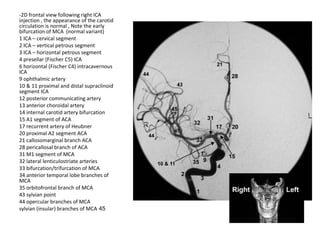

-2D frontal view following right ICA

injection , the appearance of the carotid

circulation is normal , Note the early

bifurcation of MCA (normal variant)

1 ICA – cervical segment

2 ICA – vertical petrous segment

3 ICA – horizontal petrous segment

4 presellar (Fischer C5) ICA

6 horizontal (Fischer C4) intracavernous

ICA

9 ophthalmic artery

10 & 11 proximal and distal supraclinoid

segment ICA

12 posterior communicating artery

13 anterior choroidal artery

14 internal carotid artery bifurcation

15 A1 segment of ACA

17 recurrent artery of Heubner

20 proximal A2 segment ACA

21 callosomarginal branch ACA

28 pericallosal branch of ACA

31 M1 segment of MCA

32 lateral lenticulostriate arteries

33 bifurcation/trifurcation of MCA

34 anterior temporal lobe branches of

MCA

35 orbitofrontal branch of MCA

43 sylvian point

44 opercular branches of MCA

45sylvian (insular) branches of MCA